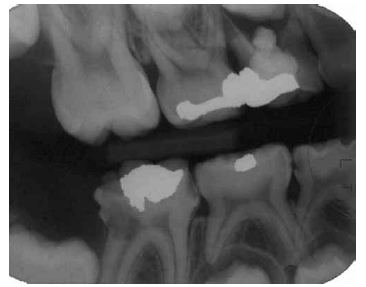

Uma paciente de 10 anos de idade procura tratamento queixandose de dor na região superior direita na região dos molares decíduos. Apresentou durante a consulta radiografia bite-wing recente da região. Considerando essas informações e a imagem radiográfica acima, julgue os itens abaixo.

I É necessário fazer uma tomada radiográfica panorâmica para melhor estabelecer o plano de tratamento.

II O dente 16 apresenta comprometimento mesial e distal por lesão cariosa e provavelmente necessitará de uma coroa total.

III O dente 84 poderá ser restaurado com um material ionomérico modificado por resina.

IV O dente 64 deverá ser extraído, devido ao extravazamento do material obturador.

A quantidade de itens certos é igual a